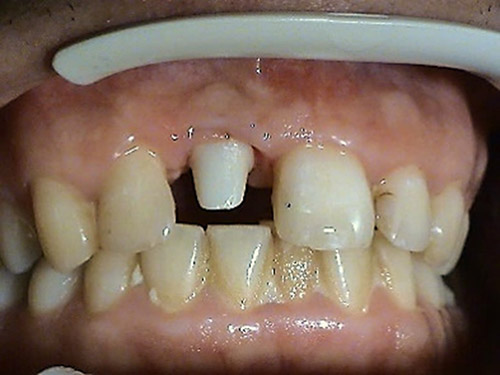

1. PHASE – implant insertion